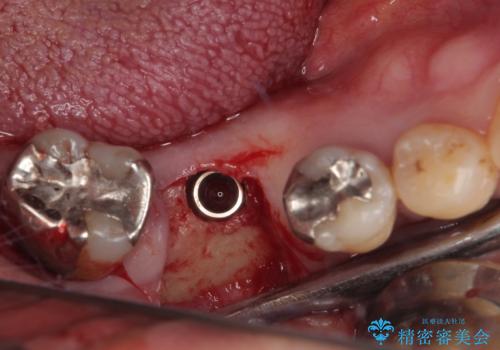

抜歯して放置したままの奥歯 即時荷重インプラント

- 奥歯を抜歯してから放置しているとのことで来院された患者様です。

歯が割れて抜歯になってしまったとのことで、咬合力に抵抗できるよう、インプラントによる補綴治療を行うこととしました。

むし歯の放置期間と抜歯してからの放置期間が長く、咬み合わせる上顎の歯がやや伸び出している状態でした。

上顎の部分矯正や対合歯の補綴治療も提案しましたが、今回は欠損部のみの治療を行いました。